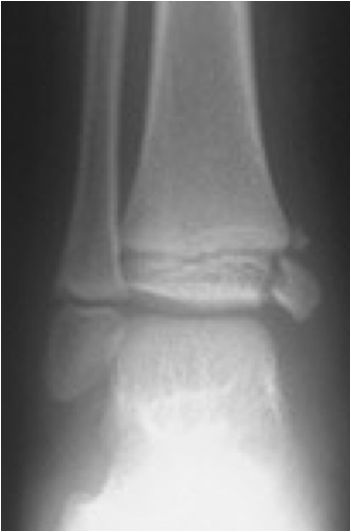

Fig. 10. Diagram showing the growth plate fracture types according to the classification by Salter and Harris (from Wikipedia).

Fig. 11. Growth plate fracture with involvement of metaphysis and epiphyis (Salter-Harris type IV.